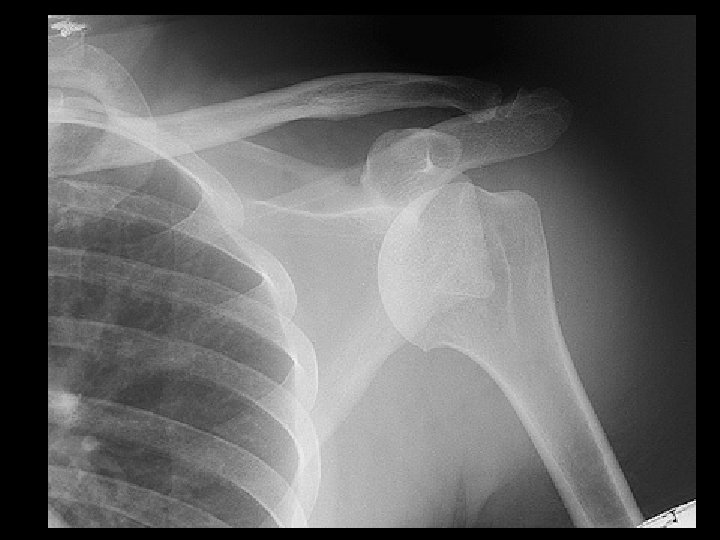

Anterior shoulder dislocation • Findings: – inferomedial, subcoracoid position of the humeral head – too much overlap of humeral head and glenoid – axillary view shows Hill Sachs - Bankhart configuration • ddx: – NONE! – This is an Aunt Minnie!